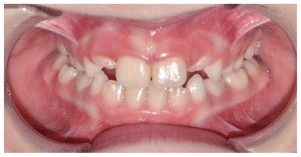

The patient was a growing female child who presented during early mixed dentition with an anterior crossbite associated with a deep overbite and a marked sagittal discrepancy (Figures 12–19). The initial clinical examination revealed a negative overjet, complete anterior deep bite, and a functional Class III occlusal pattern. Extraoral assessment showed a flattened facial profile, while cephalometric analysis confirmed a skeletal imbalance characterized by increased SNA and SNB values, an ANB of 0°, negative Withs appraisal, and significant dentoalveolar compensations, including proclination of both upper and lower incisors (Table 3). The vertical pattern was predominantly hypodivergent, suggesting a high risk of unfavorable mandibular growth progression if left untreated. Given the patient’s young age and growth potential, an early interceptive treatment was planned to use the AMCOP® TC appliance, with the aim of correcting the anterior crossbite, improving neuromuscular balance, and guiding sagittal and vertical development during growth. The appliance was worn nightly and for additional daytime hours, according to patient compliance.

After 18 months of treatment, a clear clinical improvement was observed. Intraoral examination demonstrated complete correction of the anterior crossbite, with establishment of a positive overjet and normalization of the anterior occlusal relationship. The deep bite was reduced, allowing more functional anterior guidance. Occlusal relationships improved toward a stable dental Class I, and the need for excessive dentoalveolar compensation was reduced. Cephalometric reassessment showed an overall improvement in sagittal relationships and incisor inclinations, with a trend toward normalization of the previously altered parameters. These findings indicate that early functional therapy with the AMCOP® TC appliance was effective in intercepting the developing Class III malocclusion, improving occlusal function, and potentially reducing the severity of future skeletal discrepancies (Table 4).